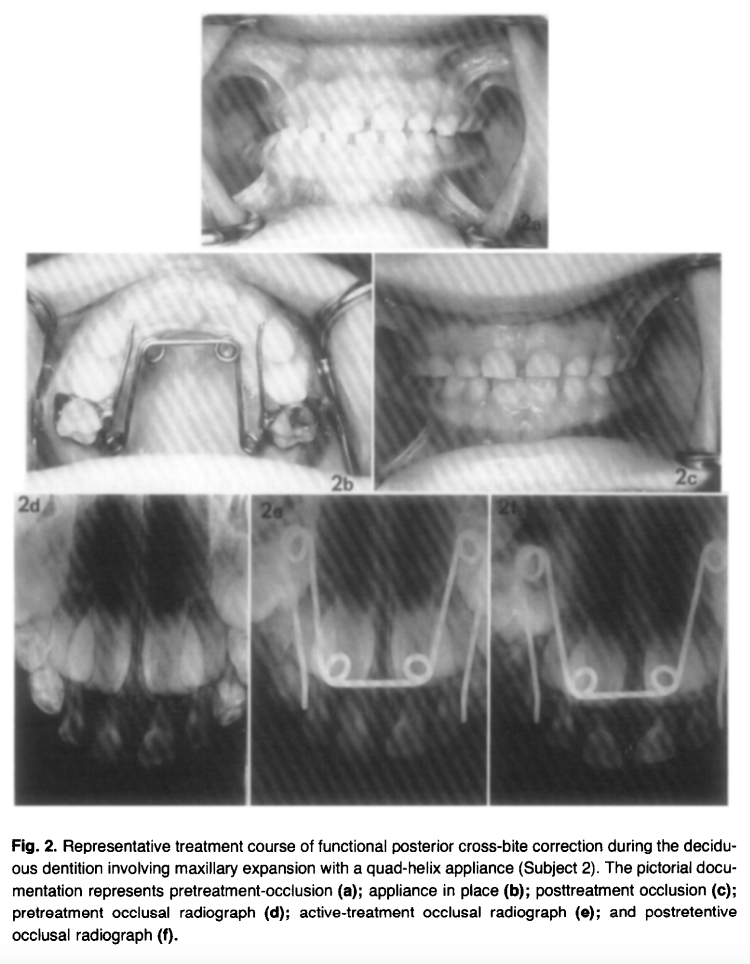

Every single subject (10/10) showed radiographic evidence of midpalatal suture opening on occlusal radiographs taken at 2 weeks of active treatment. The separation pattern was greatest anteriorly with a progressive posterior decrease — a classic sutural opening pattern. By end of retention, suture widening was no longer detectable radiographically, confirming bone fill-in.